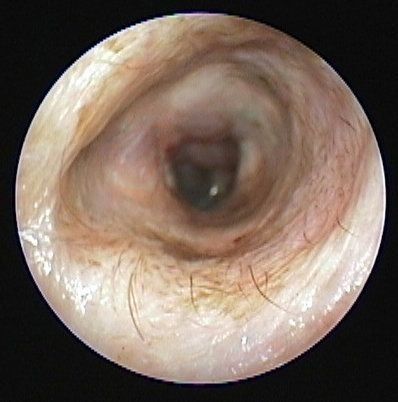

(写真上)ビデオオトスコープ(耳専用内視鏡)で見ることができる外耳道の内部です。健康な犬の耳の中は耳垢もなくきれいです。